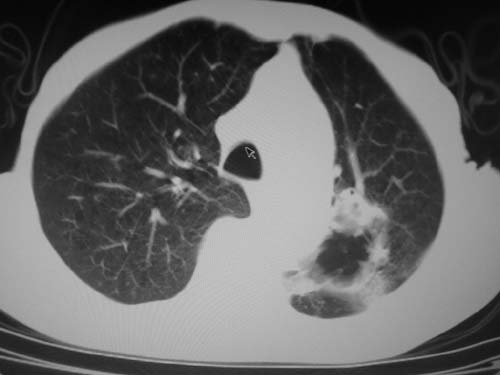

标题: CT19736:男,76岁,咳嗽,胸痛 [打印本页]

标题: CT19736:男,76岁,咳嗽,胸痛

支持左上肺周围型肺癌性并空洞形成伴胸椎转移。

左上沟癌空洞形成并胸椎转移。

考虑癌性空洞并胸椎转移。

空洞内壁有多发结节,支持癌性空洞。

支持左上肺周围型肺癌并空洞形成伴胸椎转移。z左下肺炎